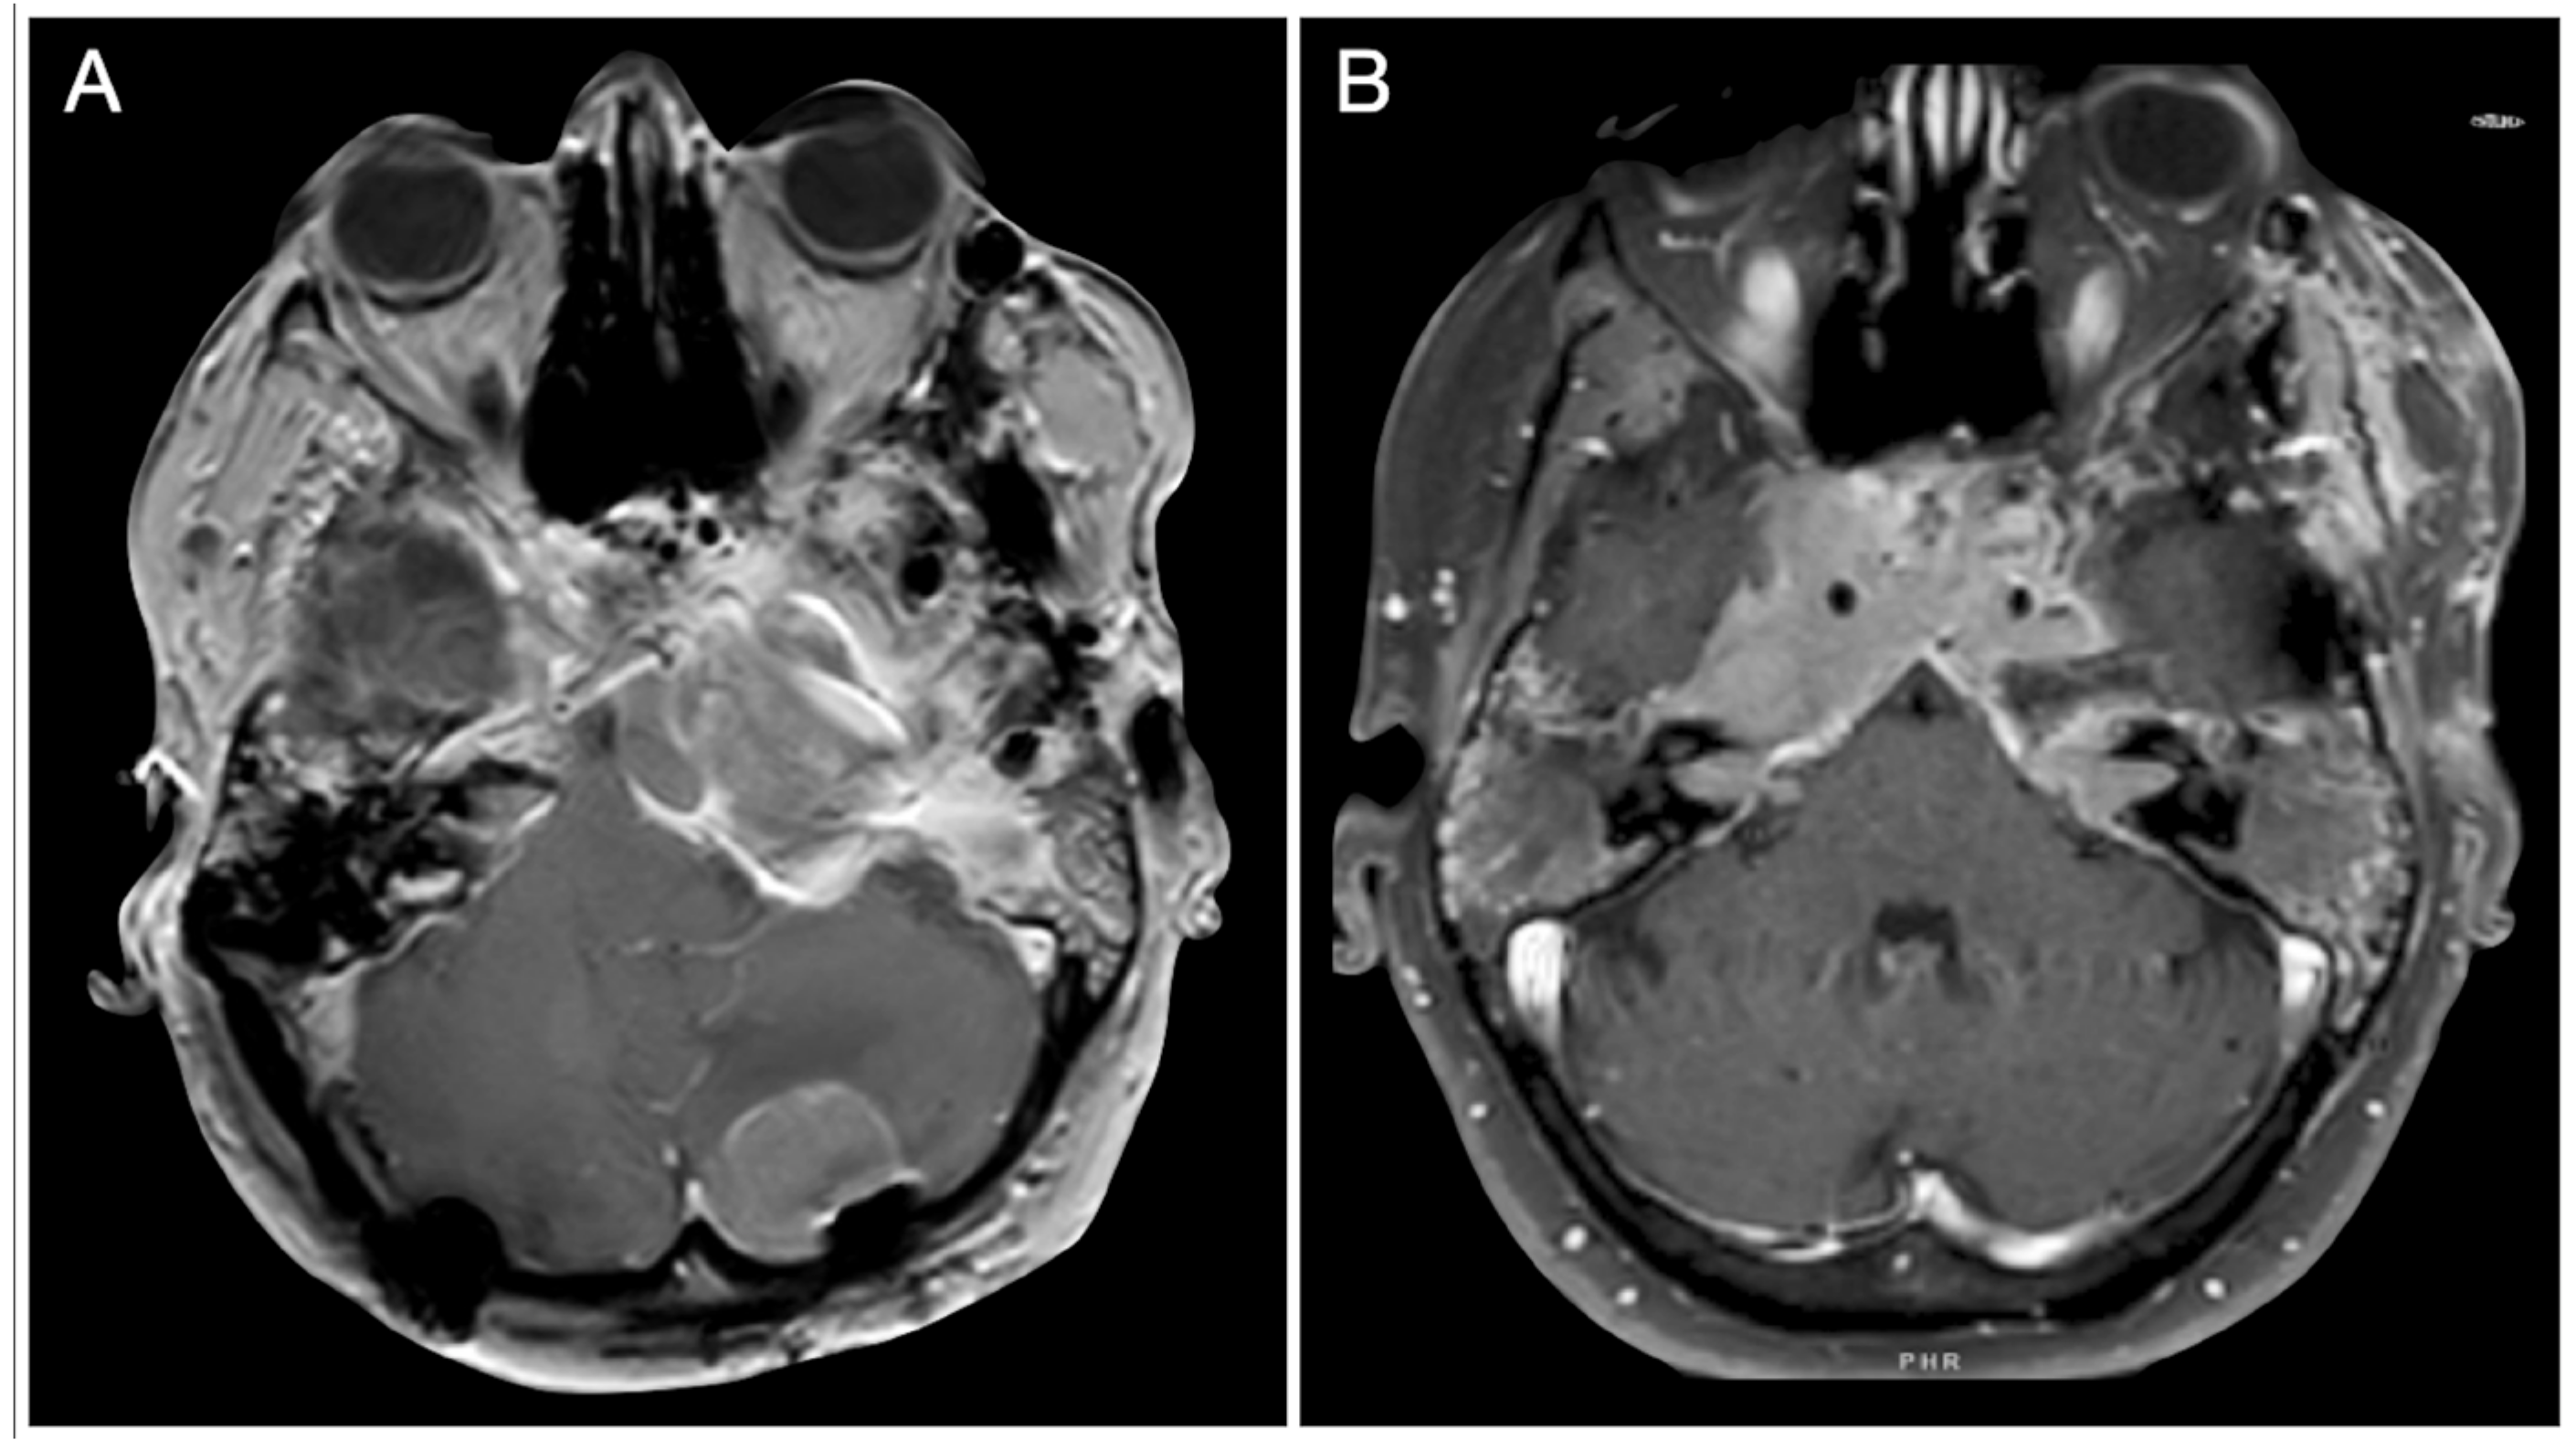

3.10. Postoperative Pituitary Apoplexy after Trans-Sphenoidal Surgery